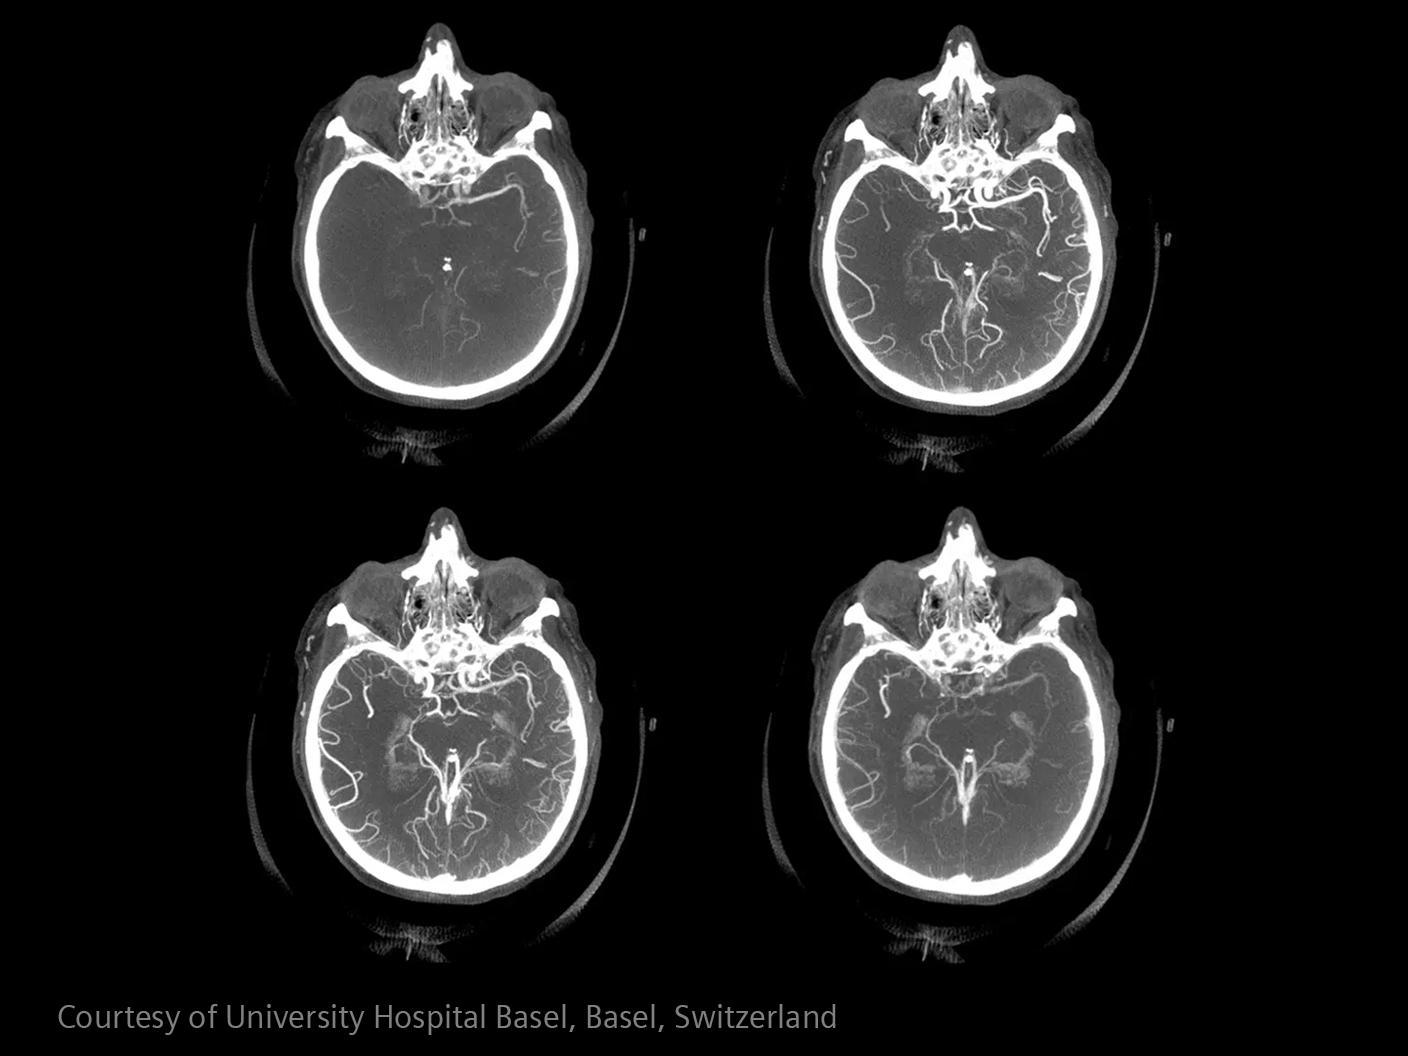

Im Bereich der Schlaganfallversorgung zählt jede Sekunde . Schnelle und präzise Bildgebung ist entscheidend, um das Ausmaß der Hirnschädigung zu beurteilen und die sofortige Behandlung einzusteuern. Angiographie, MRT, CT, Labordiagnostik und Ultraschall sind unverzichtbare Werkzeuge, um Schlaganfalltyp, -bereich und -schwere zu bestimmen. Durch technologische Fortschritte in der Bildgebung sind heute noch schnellere Aufnahmen, eine bessere Auflösung und eine optimierte Darstellung von Gehirnstrukturen und Blutgefäßen möglich. Innovationen wie Perfusionsbildgebung, Echtzeit-Gefäßkartierung und KI-gestützte Diagnostik revolutionieren die Abläufe bei Schlaganfällen und ermöglichen präzise zeitnahe Interventionen.